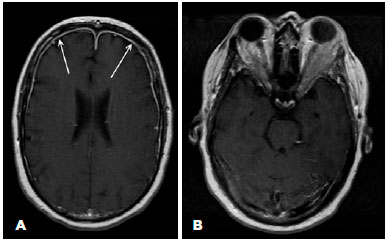

Brain magnetic resonance imaging (MRI) revealed meningeal thickening, which was strongly enhanced by contrast, mainly in the bilateral frontal region, affecting the orbital apex. Also, diffuse fat infiltration was evident in both the lateral orbit areas (Figure 1).

MRI was fundamental for the diagnosis; it revealed areas of dural thickening. The lesions were enhanced due to contrast administration(1-4,7,9). MRI can also be useful for follow-ups(1,2). CSF usually presents with normal opening pressure, elevated protein levels, and increased cellularity at the expense of lymphocytes(1,2,6,9). In addition, ESR and CRP levels are often elevated(1,2,6,9). In our patient, MRI revealed typical IHP findings. Also, ESR and CRP levels and CSF evaluation findings were all consistent with the diagnosis of IHP.